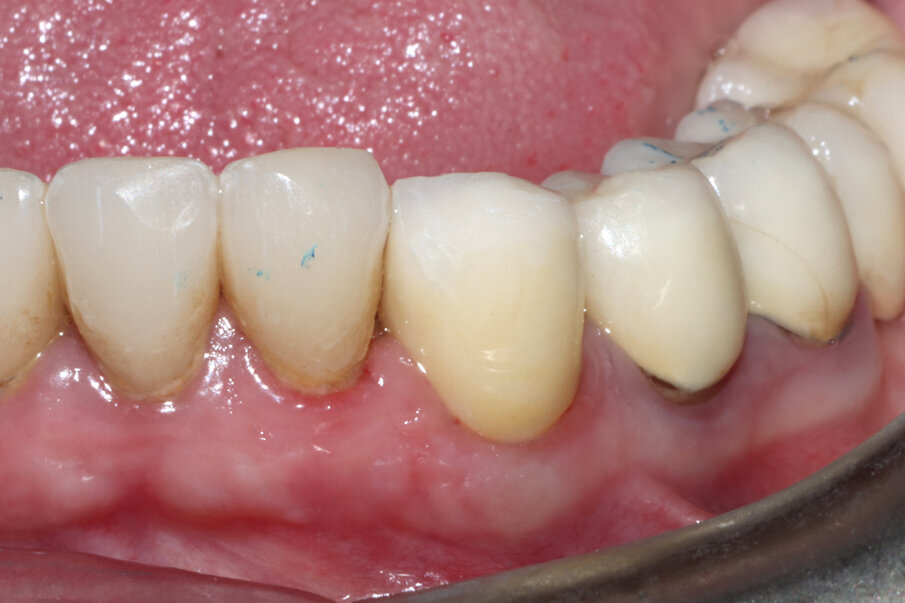

Fig. 3_Il caso clinico descritto: elemento 3.3 già rivestito di corona protesica, vitale e dolente.

Figg. 18, 19_Visione laterale dei tessuti guariti e alla consegna della corona; si noti la presenza delle papille.